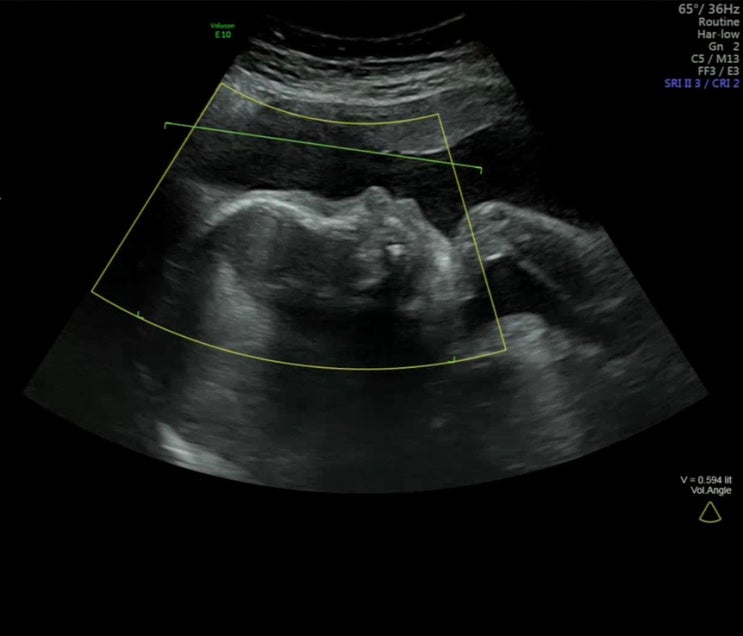

임신 24주~27주차 기록_임당검사, 입체초음파

임신 24주~27주차 기록 애기가 근육이 많이 붙었는지 태동이 점점 잘 느껴져 신기하고 재밌는 임신 중기 끝...